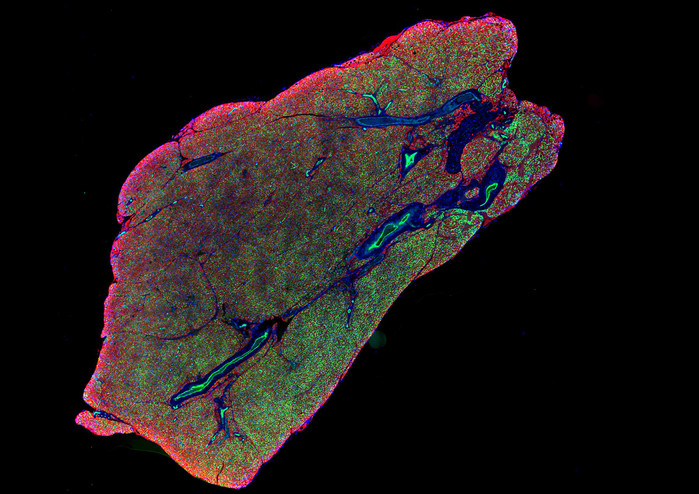

선명한 색감의 위성 사진처럼 보이는 대륙의 모습은 사실 우리 몸속 미세한 부분, 즉 혈관과 신경이 촘촘하게 얽혀 있는 갈색 지방 조직의 모습이다.

| ▲ 갈색 지방 조직의 형광 현미경 이미지. © Shamsi Lab, NYU College of Dentistry |